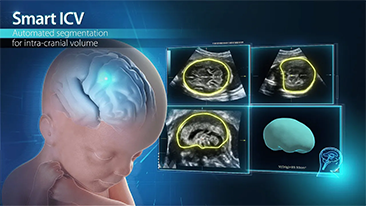

Los flujos de trabajo de OBG optimizados son necesarios para admitir grandes cantidades de pacientes para las visitas de evaluaciĂłn de la salud de las mujeres. Por ejemplo, las malformaciones del sistema nervioso central (SNC) son una de las anomalĂas congĂ©nitas mĂĄs comunes. Debido a las diversas condiciones del diagnĂłstico por imĂĄgenes, como una posiciĂłn fetal deficiente, el plano sagital medio (MSP) es particularmente difĂcil de obtener a partir de una ecografĂa 2D. Por lo tanto, la detecciĂłn y las mediciones automatizadas pueden mejorar en gran medida la eficiencia de la exploraciĂłn.